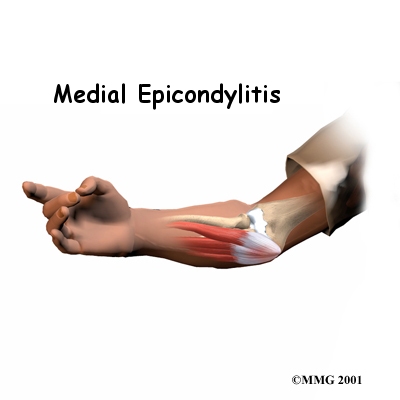

Medial epicondylitis is commonly known as golfer's elbow. This does not mean that only golfers have this condition. But the golf swing is a common cause of medial epicondylitis. Many other repetitive activities can also lead to golfer's elbow: throwing, chopping wood with an ax, running a chain saw, and using many types of hand tools. Any activities that stress the same forearm muscles can cause symptoms of golfer's elbow.

Golfer's elbow causes pain that starts on the inside bump of the elbow, the medial epicondyle. Wrist flexors are the muscles of the forearm that pull the hand forward. The wrist flexors are on the palm side of the forearm. Most of the wrist flexors attach to one main tendon on the medial epicondyle. This tendon is called the common flexor tendon.

The main symptom of golfer's elbow is tenderness and pain at the medial epicondyle of the elbow. Pain usually starts at the medial epicondyle and may spread down the forearm. Bending your wrist, twisting your forearm down, or grasping objects can make the pain worse. You may feel less strength when grasping items or squeezing your hand into a fist.